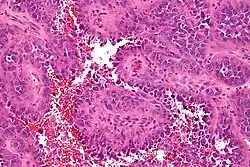

![]() Fotografía microscópica de un angiosarcoma | ||

El angiosarcoma es un tipo de cáncer que se origina en la capa más interna - endotelio - de los vasos sanguíneos, o vasos linfáticos, de cualquier tejido del organismo.[1] Es una variedad de sarcoma poco frecuente que representa el 2% del total de sarcomas extirpados.[2][3]